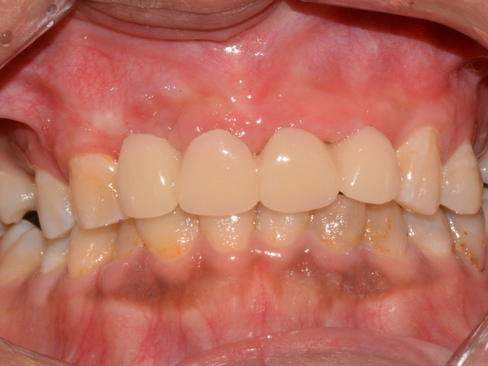

3 Weeks after healing abutment placed

Impression to fabricated provisional bridge

Prior provisional placement thick soft tissue label to Implants

Screw retained provisional bridge to form soft tissue emergence profile to take final impression in 2-3 months after soft tissue achieves pleasing emergence profile.